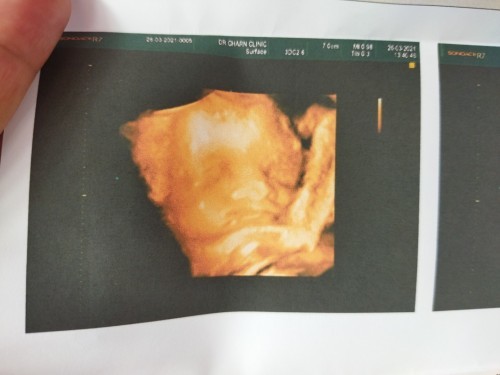

ลูกสาวสมใจอิเเม่

สมใจคุณเเม่เลยคร้า🥰

แม่ท้อง